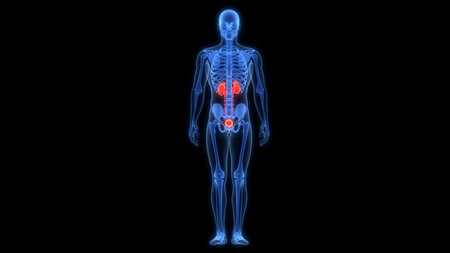

X-ray of human body with highlighted kidney, 3D illustration